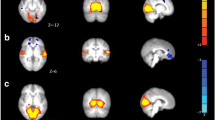

Voxel-wise comparison of the amplitude of resting activity

The voxel-wise comparison of the amplitude of resting activity showed higher amplitudes (p < 0.05, corrected for multiple comparisons) in the left parietal lobe in all frequency ranges in MWA compared to MWoA. In addition, in the 0.08–0.04 Hz frequency band the amplitudes were higher in the bilateral cerebellum, in the left occipital pole and occipito-temporal junction, and a smaller cluster was found in the right inferior parietal lobule. In the 0.04–0.02 Hz frequency band the amplitudes were higher in MWA compared to MWoA in the left inferior parietal lobule, bilateral cerebellum and in the anterior cingulate gyrus. In the 0.02–0.01 Hz range next to the inferior parietal lobule, occipital pole and cingulate gyral differences amplitudes were found higher in the bilateral frontal lobe around the superior frontal sulcus and precentral gyrus (Table 2 and Fig. 3).

The frequency specific voxel wise comparison of the amplitude of the resting activity showed higher amplitudes in MWA as compared to MWoA in all freqeuncy ranges. The voxel wise changes in each frequency range. The images are thresholded at p < 0.05 corrected for multiple comparisons and overlaid on the standard MNI_152 brain. We marked the sidedness with 'R' as the right side. The X-Y-Z letters indicates the axes of the pictures above them

There were no differences between the MWoA and healthy group or between the MWA and control group.